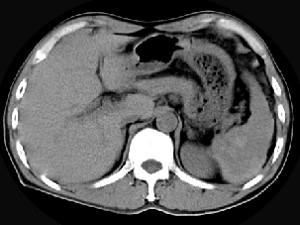

问题 男,55岁,左上中腹部突发性疼痛,CT扫描如图,最可能的诊断是 ( )

选项 A、脾脓肿 B、脾转移瘤 C、脾淋巴瘤 D、脾血管瘤 E、脾肿瘤破裂出血

答案 E